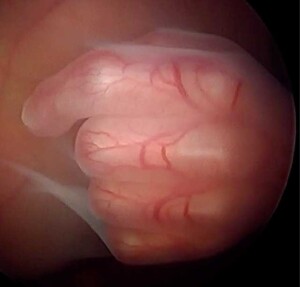

La cirugía de mínima invasión consistió en realizar una incisión en la piel para insertar una cánula hasta el interior de la cavidad uterina, a través de la cual se introduce una cámara y la fibra láser.

Por medio de la cámara se obtiene la visión directa de la placenta a través de un endoscopio y tras identificar las comunicaciones vasculares, éstas se coagulan con láser, eliminando todas las conexiones vasculares entre los fetos y dividiendo la placenta única en dos territorios placentarios independientes.